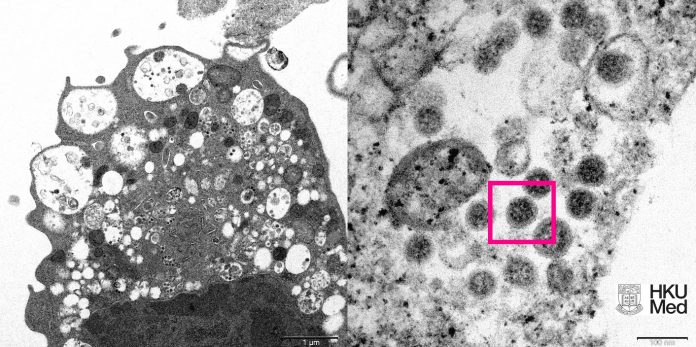

Imagem destaca variante ômicron do coronavírus feita com um microscópio

Cortesia Faculdade de Medicina da Universidade de Hong Kong